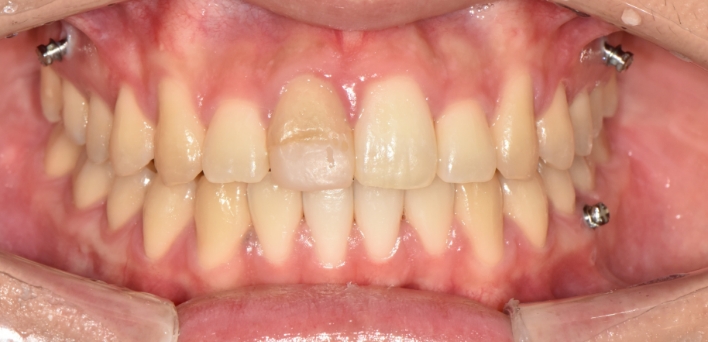

※ 더서울치과의원은 의료법을 준수하며 위 케이스는 실제 환자의 동의를 얻은 사례로 치료 전, 후가 동일한 환경에서 촬영되었습니다.

환자 케이스에 따라 부작용이 발생할 수 있습니다. 이 부분은 의료진의 충분한 상담과 체크를 통해 예방하고 줄일 수 있습니다.

[심미치료 부작용] 시술 후 치아 시림, 보철물 파손 등의 부작용이 발생할 수 있어 개인별 치아 상태에 따른 정확한 진단과 사후 관리가 중요합니다.